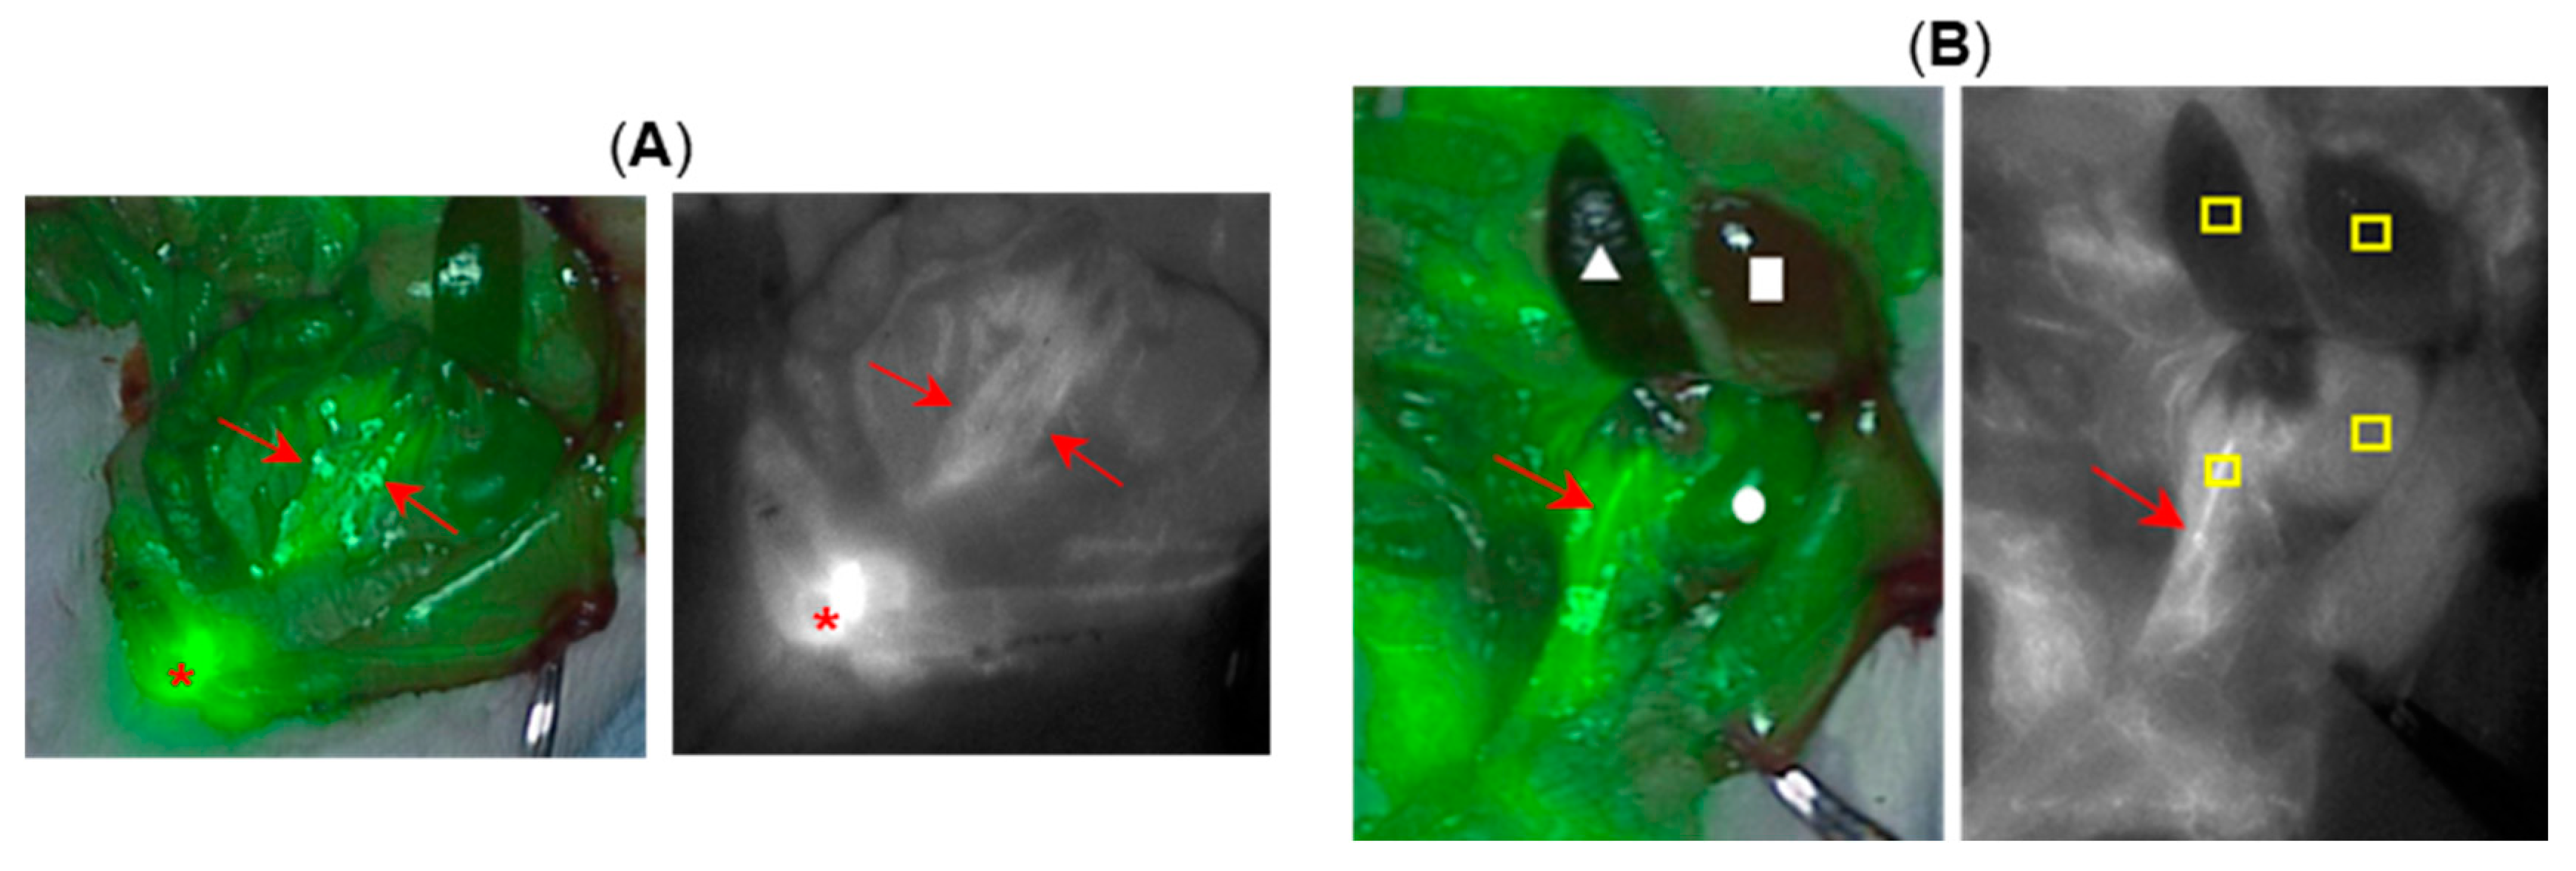

2.5. Porcine Ureter Imaging